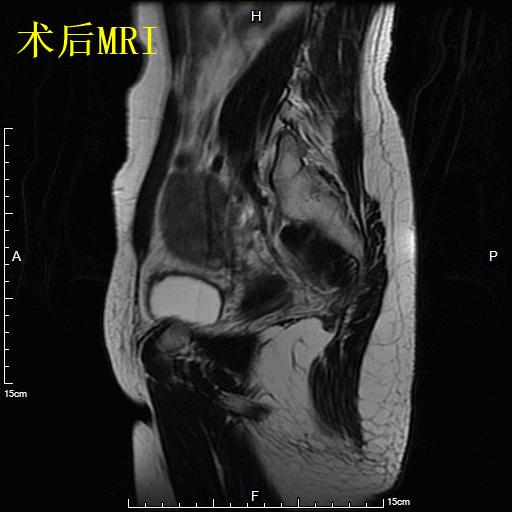

术前子宫MRI

- 对比术后6个月复查MRI显示肌瘤已明显缩小,月经量已回复正常,生活质量明显改善。

术后6个月复查子宫MRI